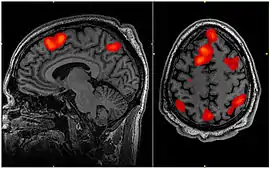

Figure 1. This is a FMRI scan of a brain during working memory task.

Many types of developmental disabilities can be traced at least partially to problems with the memory. Problems with working memory subsystems seem to lie behind the way in which patients with autism become confused over large amounts of information, and deficiencies in working memory are also implicated in attention deficit hyperactivity disorder. A number of other developmental disabilities, such as Williams Syndrome, Down syndrome, and dyslexia can also be connected with improper functioning of memory[3]. Below we focus on autism spectrum disorder (ASD) and attention deficit hyperactivity disorder (ADHD) because the role of memory in these two disorders has been studied in detail, allowing us to use them to shed light on how the memory functions in practice.

According to the World Health Organization (WHO) it estimated 1 in every 160 children will be diagnosed with Autism Spectrum Disorder (ASD) and currently 39 million individuals are living with an Attention Deficit Hyperactivity Disorder (ADHD) diagnoses [68][69]. Working Memory is a system used to implicate the process of encoding, decoding and maintenance of our memory (Figure 1)(specifically short-term memory) while , at the same time maintaining activity and accessibility [70][71]. Research suggests developmental disabilities such as those as defined in the Diagnostic Statistics Manual of ASD and ADHD impact working memory. This chapter, within the framework of Baddely's working memory model attempts to understand the inner workings of these prevalent disorders.